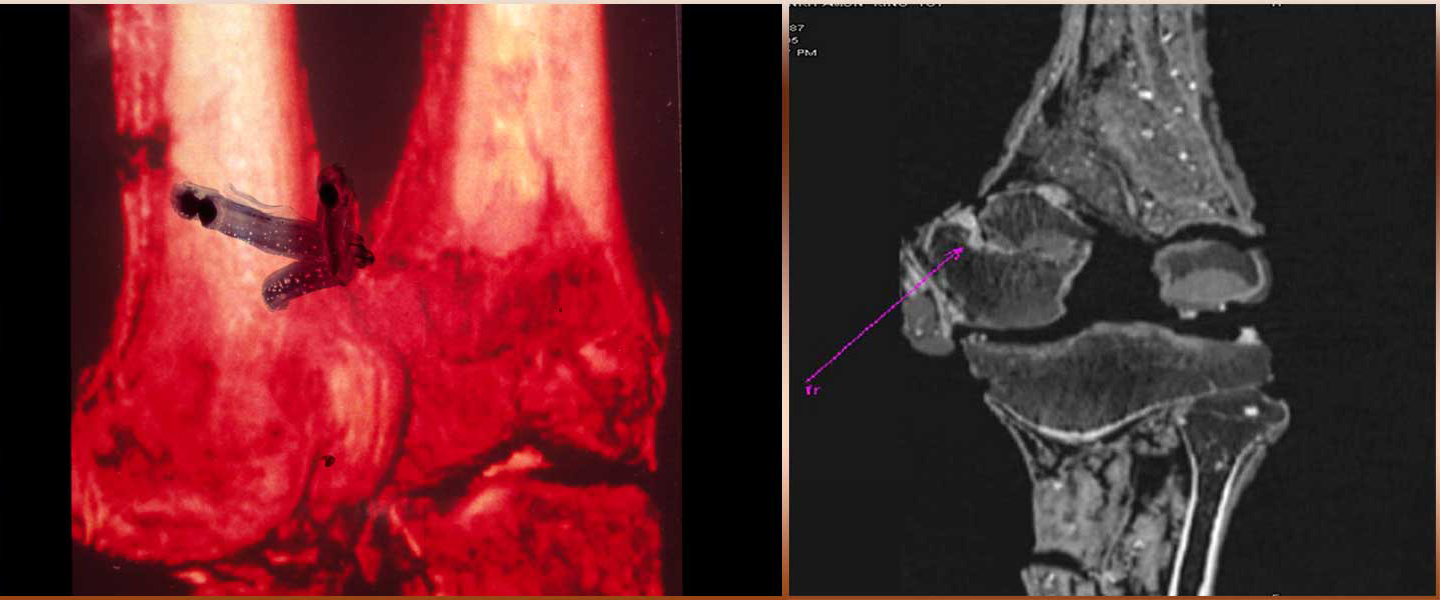

L’esame rivelò però una frattura del femore sinistro, quasi all’altezza del ginocchio (la cui rotula era allentata e fu staccata durante la prima autopsia), una frattura presumibilmente perimortem (ma questo fatto è stato contestato) – di per sé non mortale, ma la cui infezione avrebbe potuto essere fatale. Altri studiosi credono però che la frattura sia stata causata dal team di Carter (nessuna evidenza di ematoma alla TAC); la questione è aperta.

Doherty (2002) e Hawass (2010): soffriva di sindromi malformative del piede destro e piede sinistro equino, testimoniato anche dai 120 bastoni trovati nella tomba. PERÒ: nessuna evidenza nell’esame del 1925, contestazioni di esperti sul piede equino, presenza di bastoni cerimoniali in diverse altre tombe.

Le lesioni metatarsali al piede sinistro di Tutankhamon e l’accorciamento del secondo dito dello stesso piede sarebbero invece sintomi di anemia falciforme, una patologia dimostrata già nell’Egitto predinastico. Anche il prognatismo mascellare (overbite) mostrato nella scansione del 2005 sarebbe compatibile con una diagnosi di anemia falciforme (Timman e Meyer, 2010).